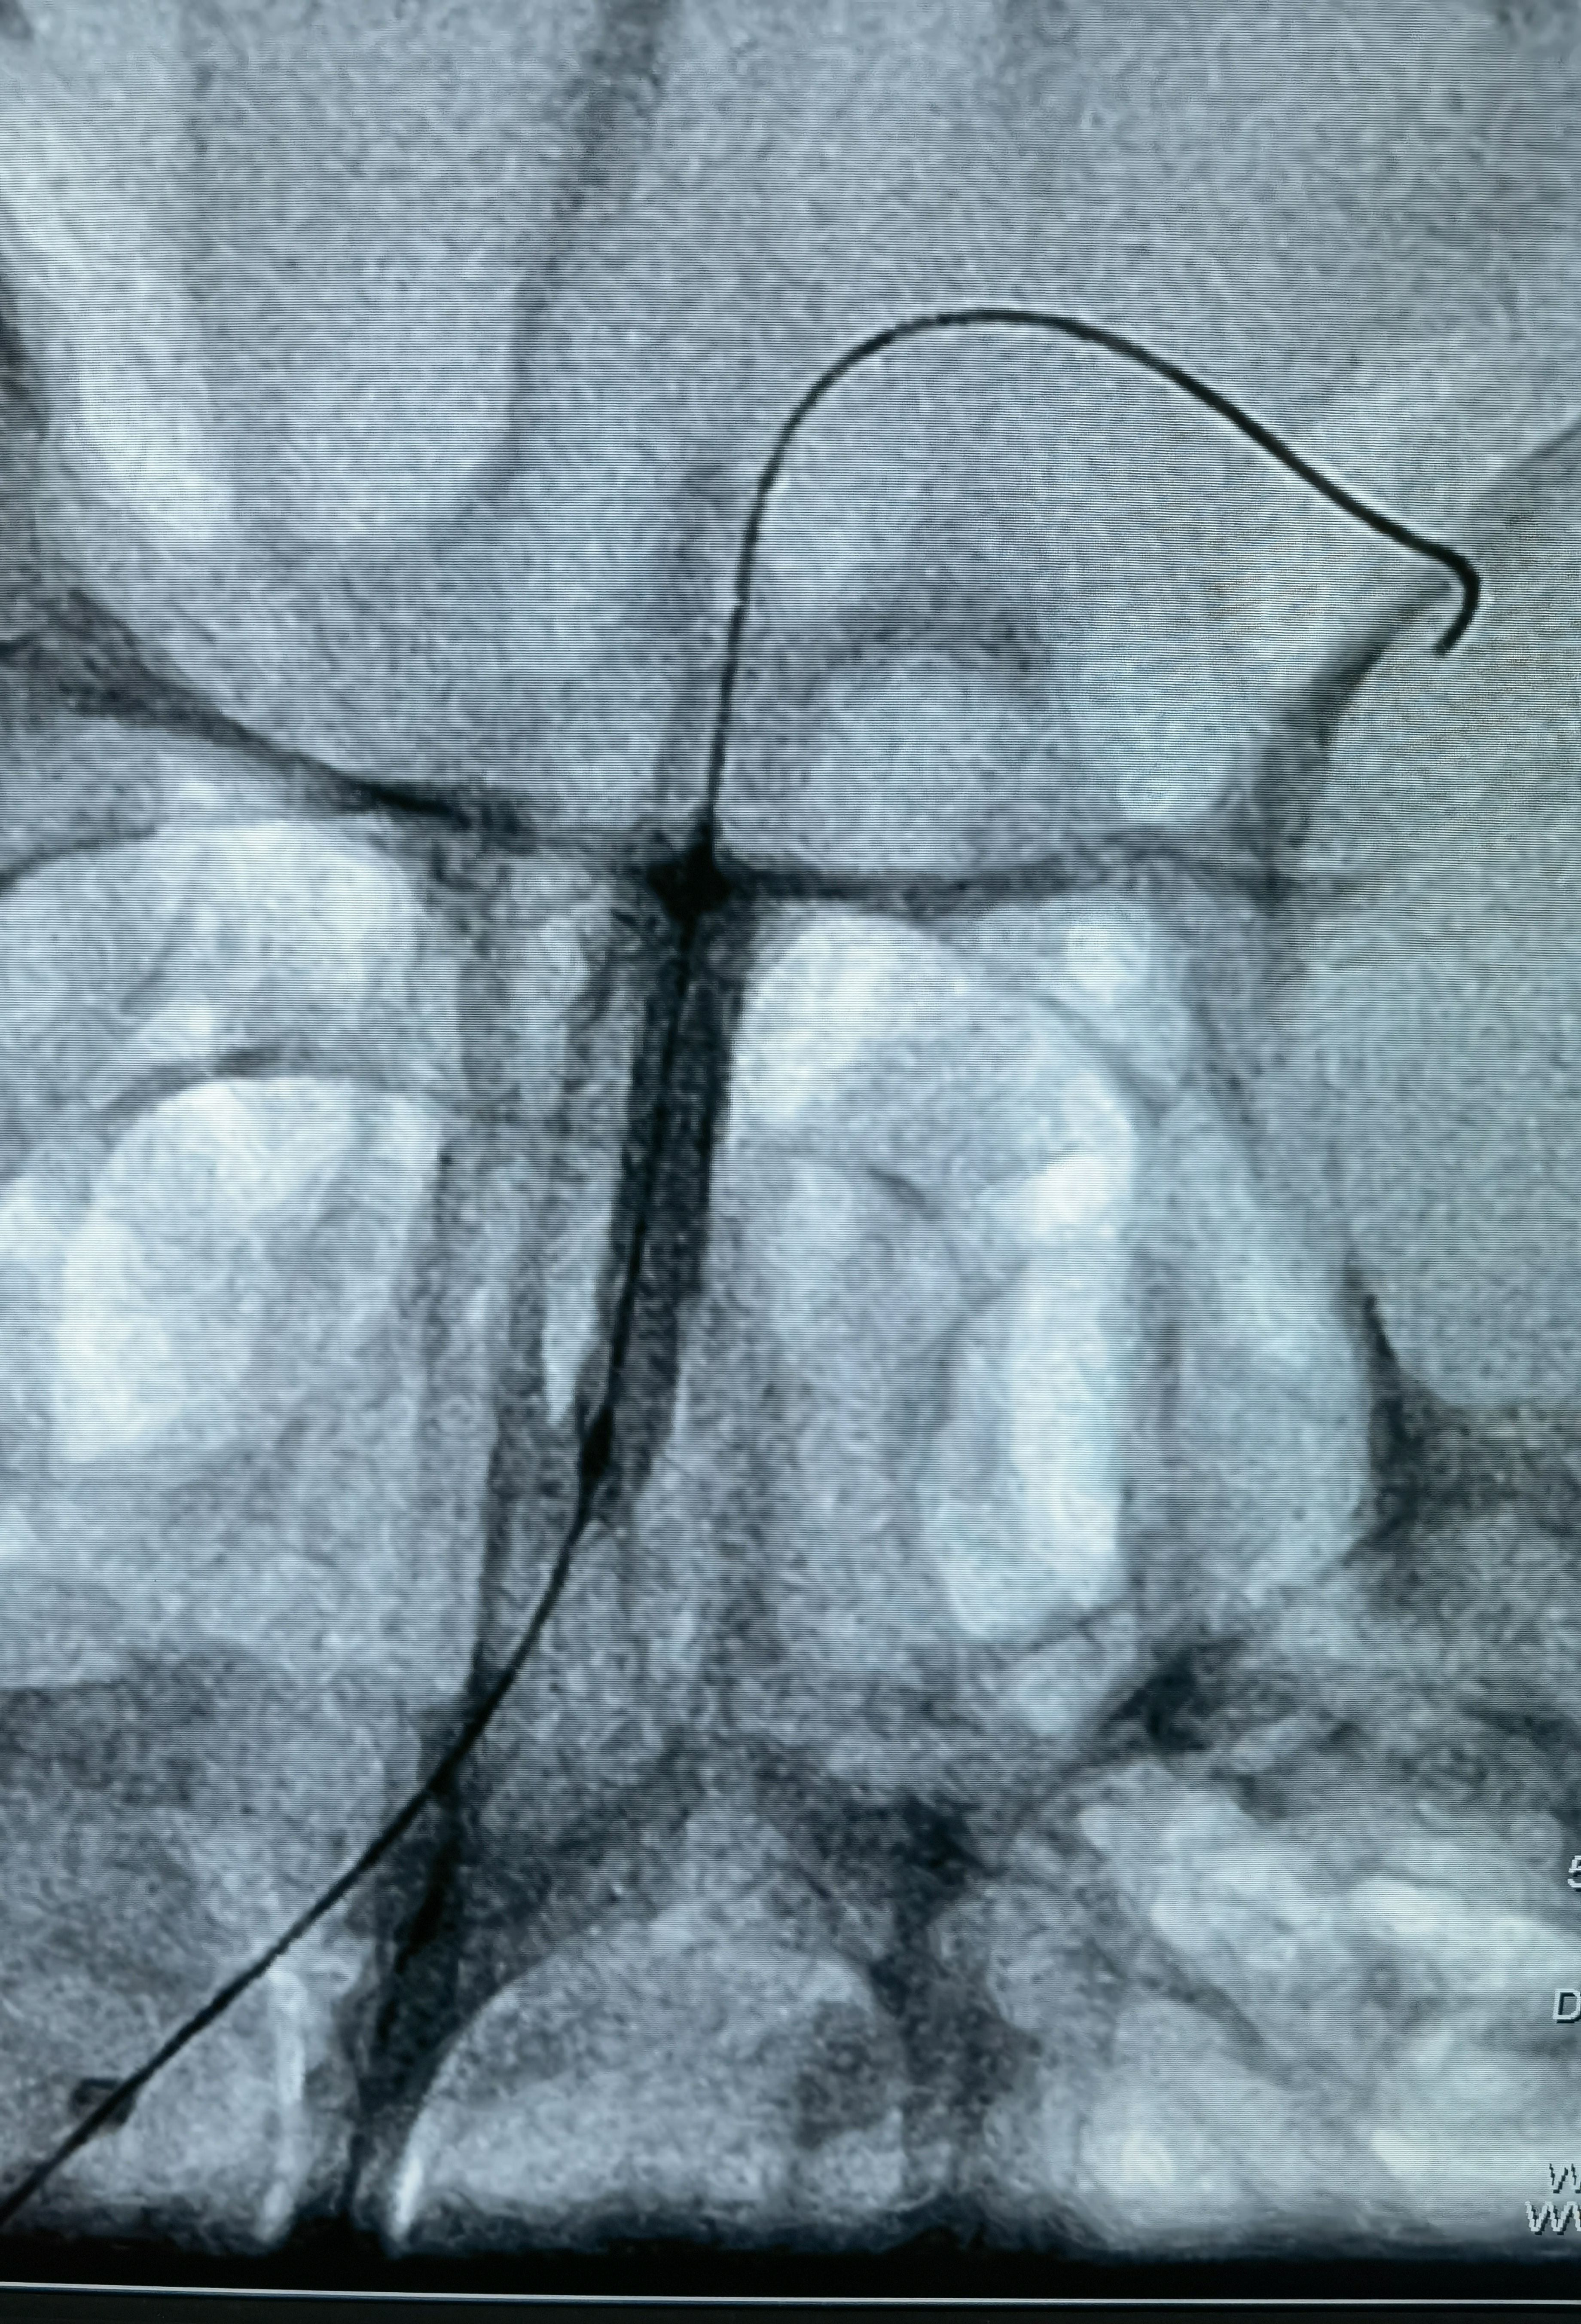

蒙片看支架打开贴壁良好

术后正位造影

术后侧位造影